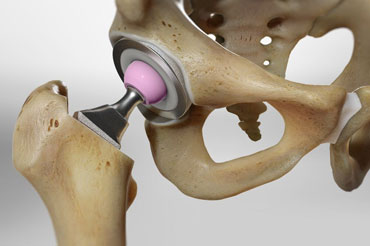

Total Hip Replacement (THR), also known as total hip arthroplasty, is a surgical procedure performed to relieve pain and improve...

Read More